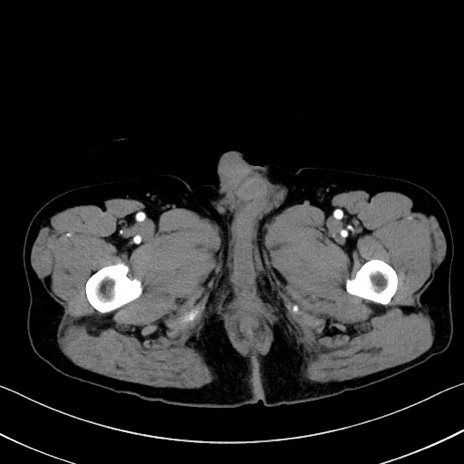

症例35(横断像)

【症例】70歳代 男性

【主訴】腹部膨満、嘔吐

【現病歴】昨日より腹部膨満感出現。本日増悪し、仙痛出現。嘔吐あり、受診。

【既往歴】糖尿病、胆摘後

【身体所見】BP 149/80mmHg、HR 74/min、BT 35.9℃、腹部:膨満、軟、圧痛なし。腸雑音減弱あり。上腹部正中切開瘢痕あり。

【データ】WBC 13500、CRP 1.72